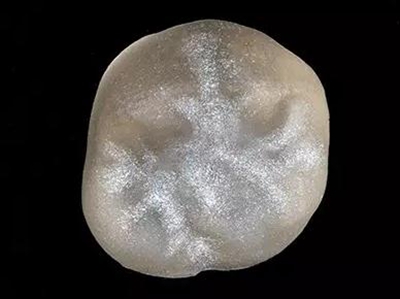

16牙位牙齿牙合面观.

牙齿经过根管治疗且充填修补,需要重新修复。